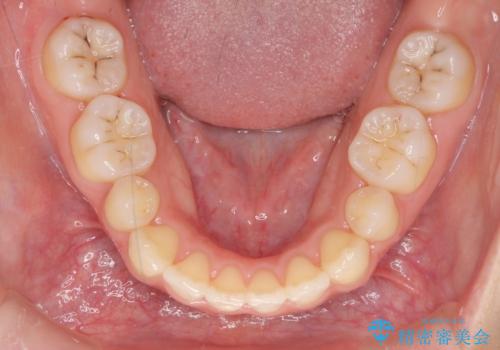

- 小さいころに小臼歯を抜歯しワイヤー矯正をしたが、すき間が空いてきて、前歯の並びが戻ってしまったとのこと。

インビザラインライトという部分矯正コースで、全体矯正に比べ、比較的安価に治療しました。

前歯の並びが格段にきれいになり、大変喜んでいただけました。